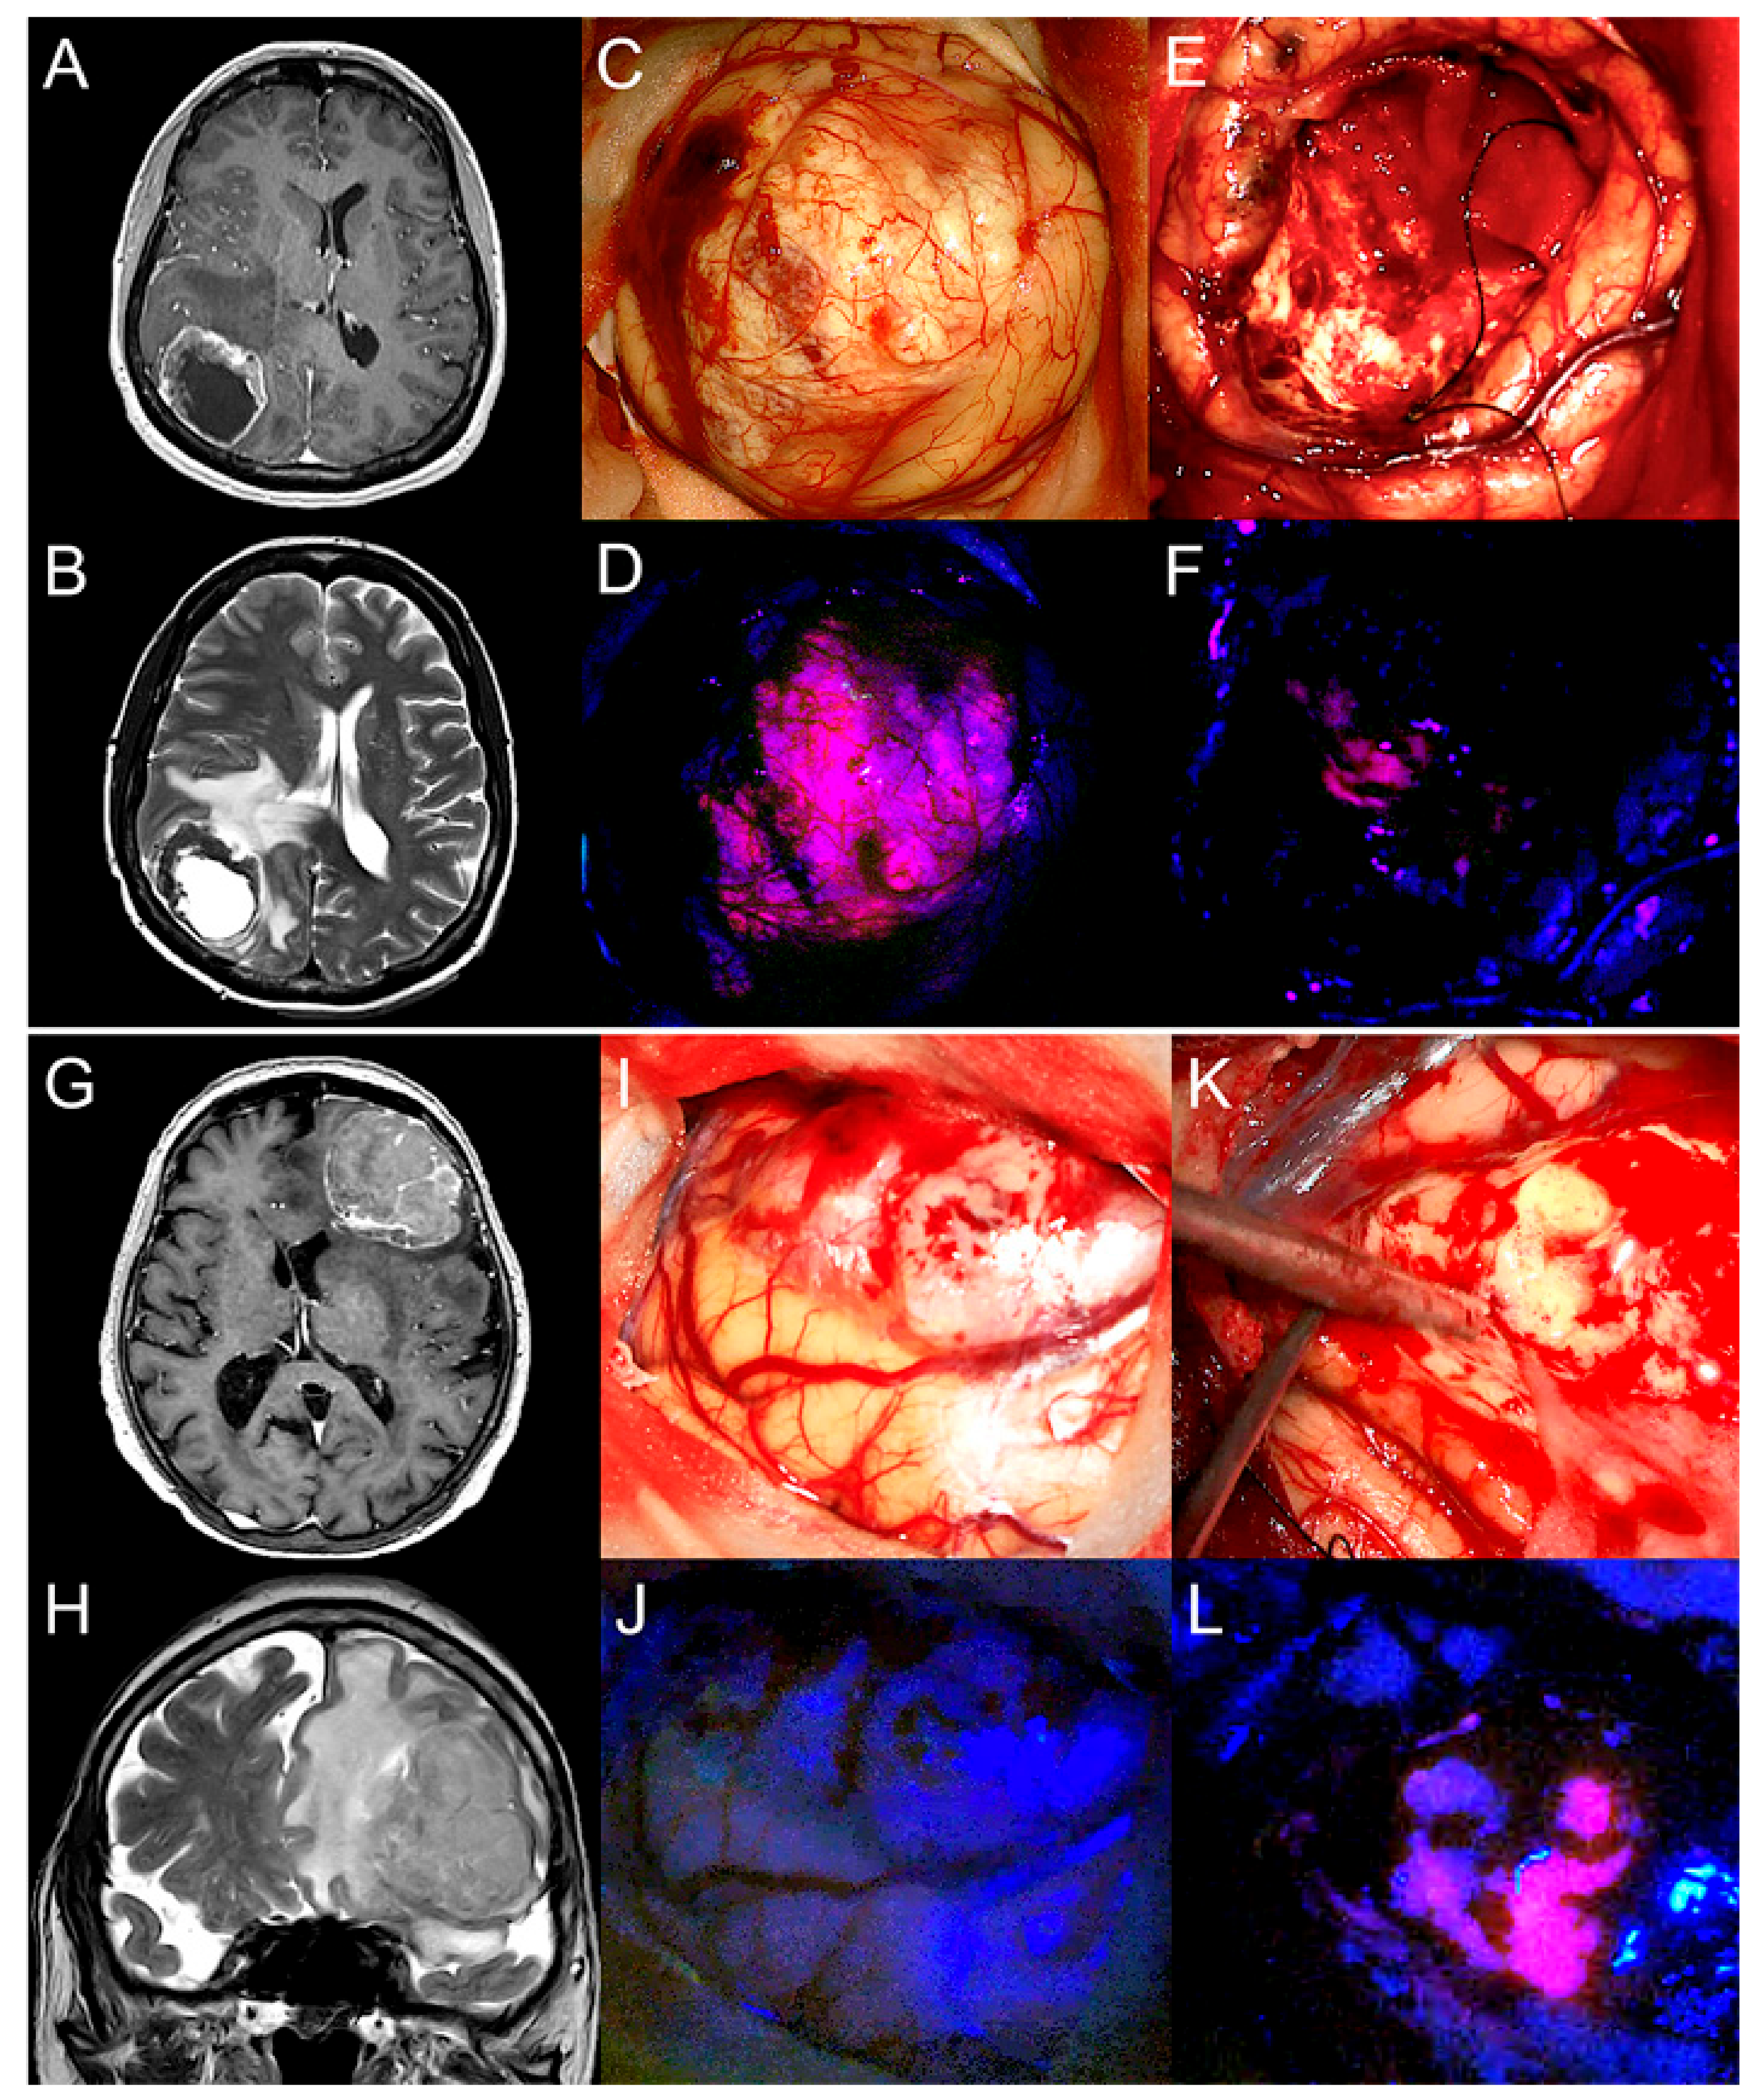

2.2. 5-ALA Fluorescence Characteristics of BM

2.3. 5-ALA Fluorescence Characteristics of Peritumoral Brain Tissue

2.4. Tissue Samples from Peritumoral Brain Tissue and Histopathology

2.4.1. Tumor Cell Infiltration

2.4.2. Angiogenesis